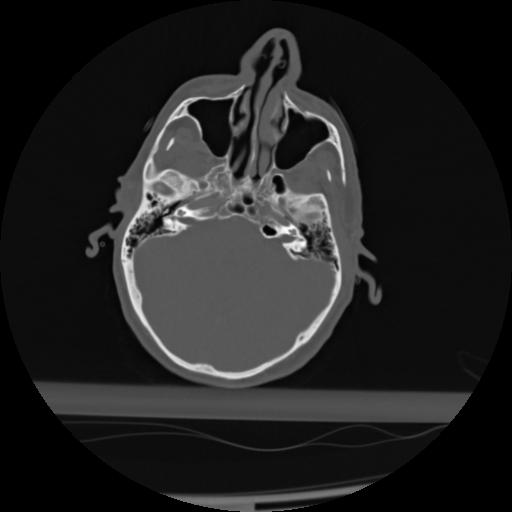

21 ANGIO,CE,Axial,3.0,ANGIO,,